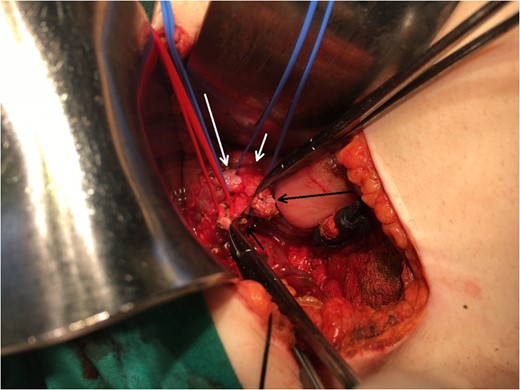

Operating field after the removal of the gallbladder. Short black arrow: the stump of the aberrant bile duct. Long black arrow: the stump of the cystic duct. Long white arrow: CHD. Short white arrow: CBD.